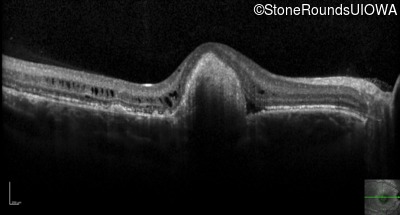

Optical Coherence Tomography - Right - 20/100 +1 sc

Exemplar / OCT Stack

OCT Stack